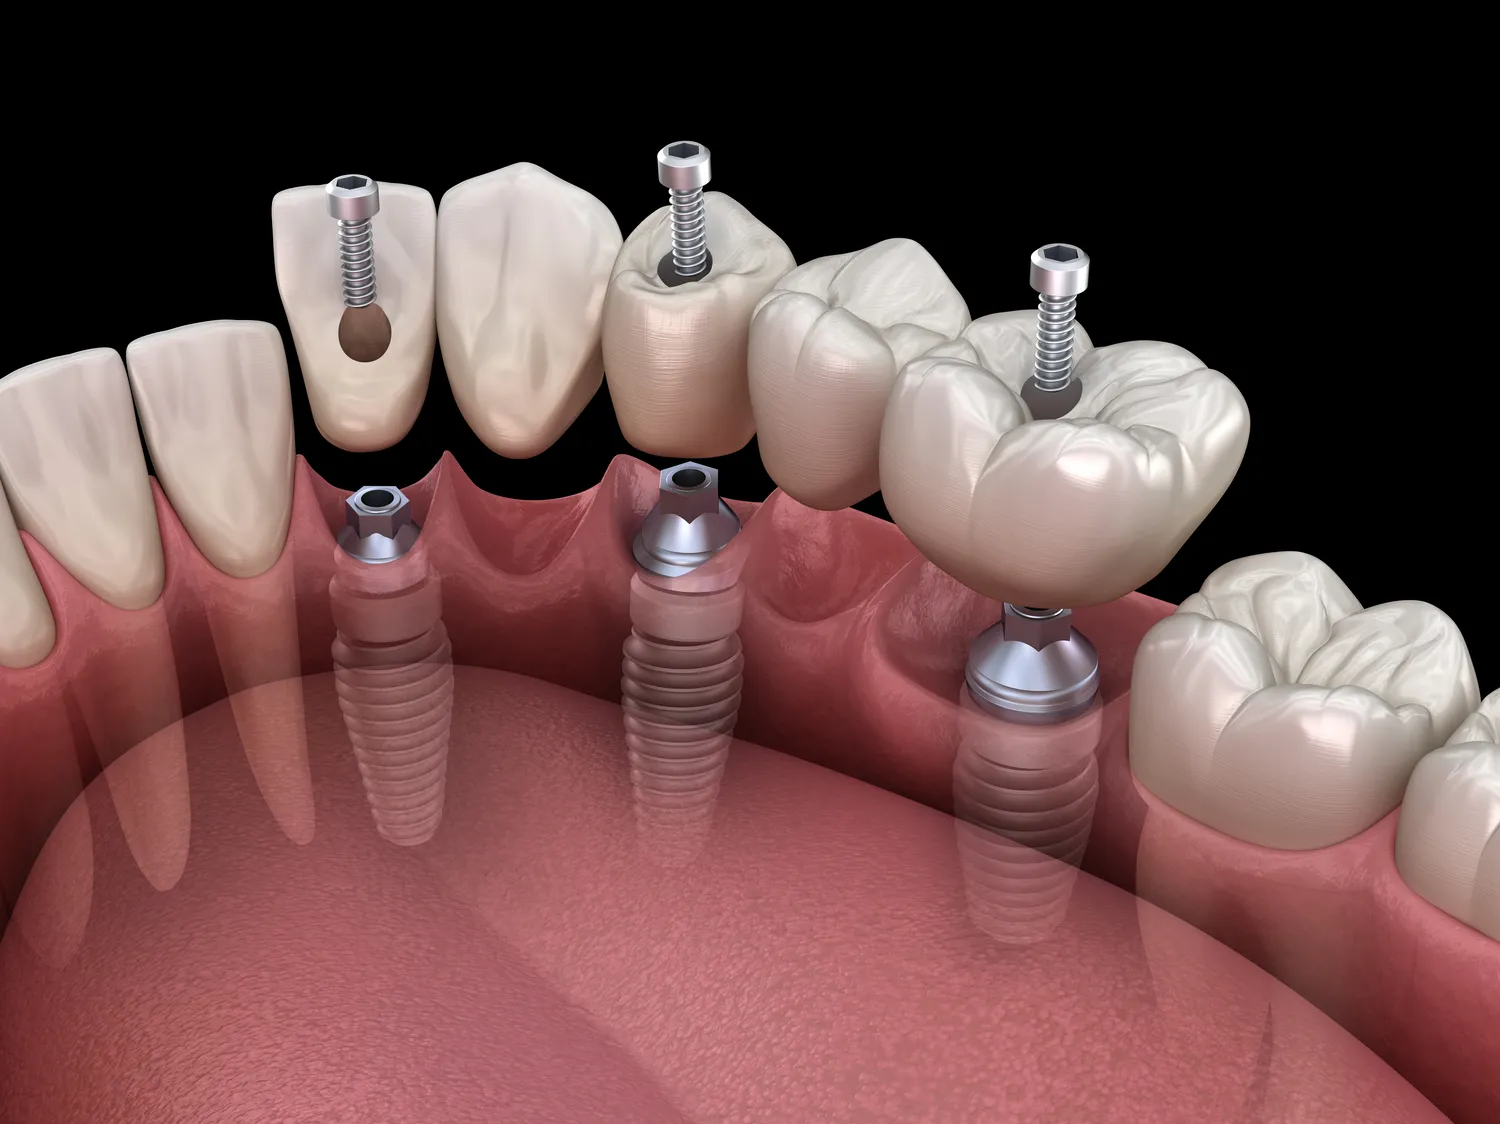

Implanty zębów to coraz popularniejsza metoda leczenia braków w uzębieniu, a ich koszt jest jednym z kluczowych czynników, które pacjenci biorą pod uwagę przy wyborze miejsca leczenia. W Turcji ceny implantów są znacznie niższe niż w wielu krajach zachodnich, co przyciąga pacjentów z całego świata. Na przykład w Stanach Zjednoczonych koszt jednego implantu może wynosić od 3000 do 4500 dolarów, podczas gdy w Turcji ceny wahają się od 300 do 800 dolarów za implant. Tak duża różnica w cenach wynika z niższych kosztów życia oraz opłat za usługi medyczne w Turcji. Warto jednak pamiętać, że cena nie zawsze idzie w parze z jakością. Wiele klinik w Turcji oferuje nowoczesny sprzęt i wysoko wykwalifikowanych specjalistów, co sprawia, że pacjenci mogą liczyć na wysoką jakość usług.

Cena implantów zębów w Turcji może być uzależniona od wielu czynników, które warto rozważyć przed podjęciem decyzji o leczeniu. Po pierwsze, rodzaj implantu ma kluczowe znaczenie dla ostatecznego kosztu. Na rynku dostępne są różne marki i modele implantów, które różnią się jakością oraz ceną. Niektóre kliniki oferują tańsze rozwiązania, które mogą nie spełniać najwyższych standardów jakości. Po drugie, doświadczenie i renoma stomatologa również wpływają na cenę zabiegu. Specjaliści z wieloletnim doświadczeniem mogą pobierać wyższe stawki za swoje usługi, co jest uzasadnione ich umiejętnościami i wiedzą. Kolejnym czynnikiem jest lokalizacja kliniki; placówki znajdujące się w większych miastach mogą mieć wyższe ceny niż te usytuowane w mniejszych miejscowościach. Oprócz tego warto zwrócić uwagę na dodatkowe koszty związane z zabiegiem, takie jak konsultacje przedoperacyjne czy ewentualne badania diagnostyczne.

Proces zakupu implantów zębów w Turcji zazwyczaj rozpoczyna się od dokładnego researchu oraz wyboru odpowiedniej kliniki stomatologicznej. Pacjenci często korzystają z internetu, aby znaleźć opinie i rekomendacje dotyczące różnych placówek oraz lekarzy. Po dokonaniu wyboru warto skontaktować się z kliniką i umówić na konsultację online lub bezpośrednią wizytę. W trakcie konsultacji lekarz przeprowadza szczegółowy wywiad medyczny oraz ocenia stan zdrowia pacjenta, co pozwala na ustalenie najlepszego planu leczenia. Następnie pacjent otrzymuje szczegółowy kosztorys oraz informacje dotyczące przebiegu zabiegu. Po zaakceptowaniu oferty następuje ustalenie terminu zabiegu oraz organizacja transportu i zakwaterowania, jeśli pacjent przyjeżdża z zagranicy. W dniu zabiegu lekarz przeprowadza niezbędne badania diagnostyczne i przystępuje do wszczepienia implantu.

Pacjenci często mają wiele pytań związanych z implantami zębów w Turcji, co jest zrozumiałe biorąc pod uwagę różnice w kosztach oraz procedurach medycznych. Jednym z najczęściej zadawanych pytań jest to, jak długo trwa proces wszczepienia implantu. Zazwyczaj cały proces, od konsultacji do zakończenia leczenia, może trwać od kilku dni do kilku tygodni, w zależności od indywidualnych potrzeb pacjenta oraz skomplikowania przypadku. Inne pytanie dotyczy bólu i dyskomfortu podczas zabiegu; wiele osób obawia się, że procedura będzie bolesna. Warto jednak zaznaczyć, że nowoczesne techniki znieczulenia sprawiają, że pacjenci rzadko odczuwają ból podczas zabiegu. Kolejnym istotnym zagadnieniem jest czas gojenia się implantu. Proces ten może trwać od kilku tygodni do kilku miesięcy, w zależności od indywidualnych predyspozycji organizmu oraz przestrzegania zaleceń lekarza.

Czas gojenia się implantów zębów może różnić się znacznie w zależności od indywidualnych predyspozycji pacjenta oraz specyfiki przeprowadzonego zabiegu. Zazwyczaj proces ten trwa od kilku tygodni do kilku miesięcy; pierwsza faza gojenia polega na integracji implantu z kością szczęki, co jest kluczowe dla jego stabilności i funkcjonalności. W większości przypadków czas ten wynosi od 3 do 6 miesięcy, jednak u niektórych pacjentów może być krótszy lub dłuższy w zależności od czynników takich jak stan zdrowia ogólnego czy jakość kości szczęki. Po zakończeniu tego etapu możliwe jest przystąpienie do kolejnej fazy leczenia – umieszczenia korony protetycznej na implancie. Warto pamiętać, że odpowiednia pielęgnacja jamy ustnej oraz przestrzeganie zaleceń lekarza mogą przyspieszyć proces gojenia się i zwiększyć szanse na sukces całej procedury.